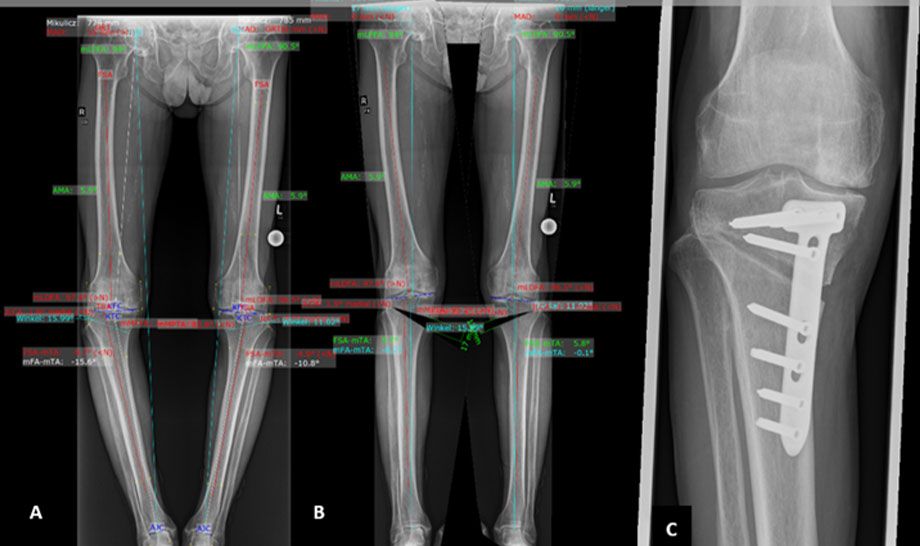

Chronische Knieschmerzen können durch eine Fehlstellung der Beinachse entstehen. Eine gezielte Achskorrektur verteilt die Belastung im Gelenk neu, lindert Schmerzen und kann den Verschleiß verlangsamen. Die HTO (High Tibial Osteotomy) korrigiert das Schienbein, wenn die Innenseite des Kniegelenks überlastet ist. Durch das Einfügen oder Entfernen kleiner Knochenkeile wird die Achse so angepasst, dass die Last gleichmäßiger verteilt wird. Die DFO (Distal Femoral Osteotomy) korrigiert den Oberschenkelknochen, wenn die Fehlstellung von dort ausgeht. Beide Verfahren entlasten das Gelenk, erhalten die natürliche Funktion und können helfen, eine spätere Knieprothese zu vermeiden.

Software gestützte Planung der Operation.

Auf dem Bild A ist die Ausgangssituation mit den O-Beinen beidseits dargestellt. Auf dem Bild B das geplante Operations-Ergebnis mit den geraden Beinachsen. Bild C: Operationsergebnis mit Osteotomie und Plattenversorgung. Die Knochenlücke füllt sich rasch mit neuem Knochen auf.